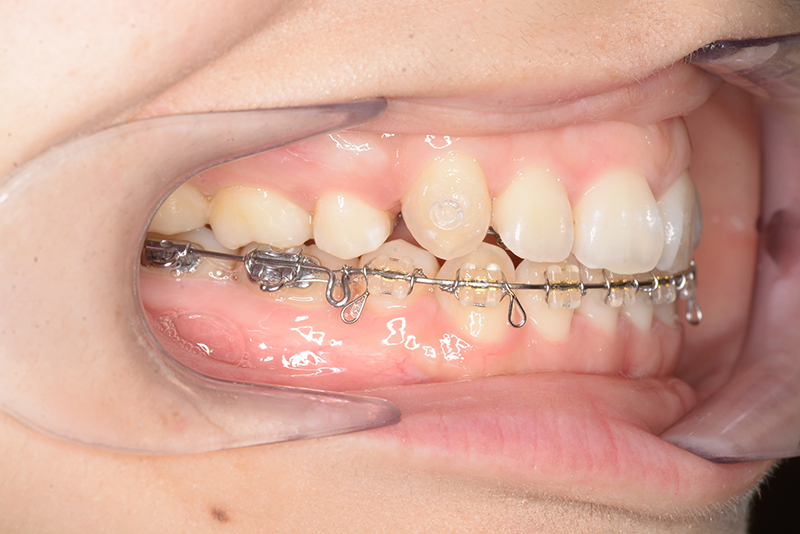

| 口腔内所見 | over jet 4.5mm、over bite 4.0mm、大臼歯関係 I級で上下顎前歯部に叢生が認められた。 |

| 批評・予后 | 叢生が大きかった影響もあり、治療期間は20ヶ月と比較的短い期間が終了できた。治療後においては口元の改善、咬合の緊密化は達成できたように思う。 |